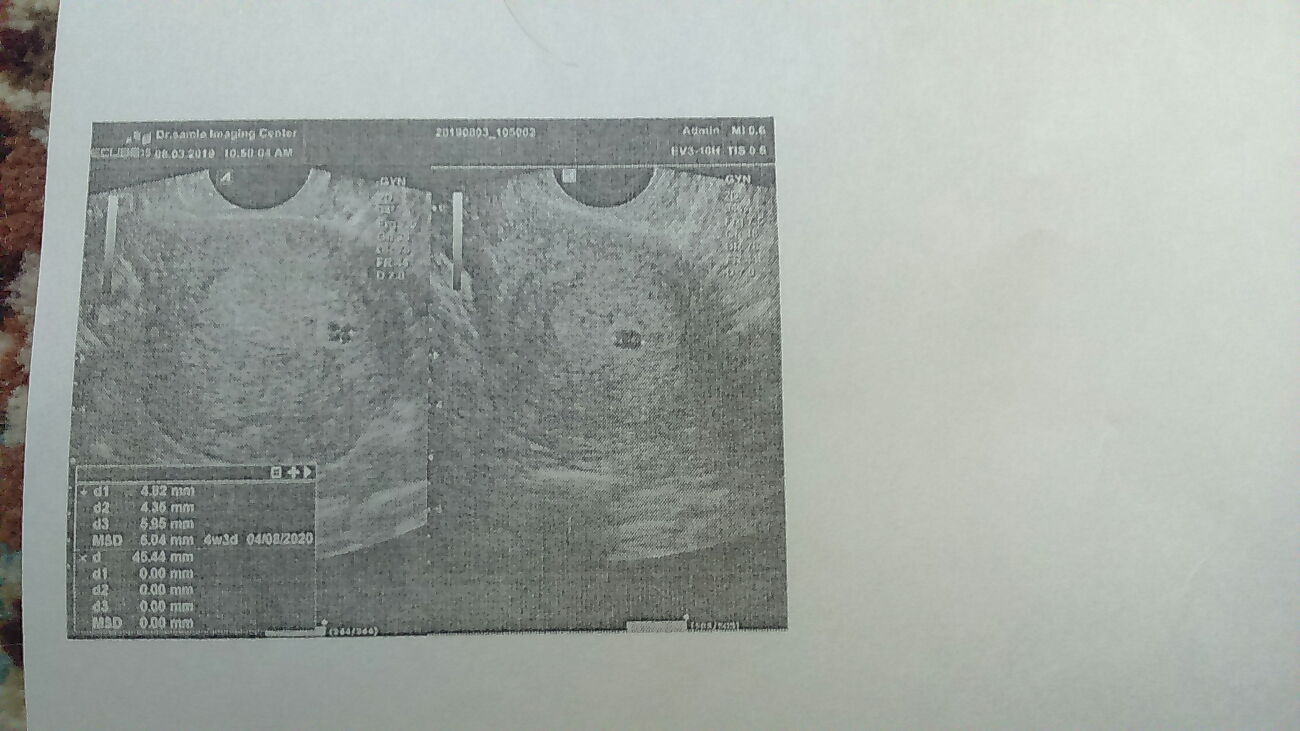

سلام ساک حاملگی برای سن ۴ هفته رویت شده ، برای قلب جنین هم که فعلا زود است دو هفته دیگه تکرار. کنید

باید صبر کنه تا جنین و ضربان قلبش تشکیل بشه خیلی زود رفتن سونو ۱۵ روز دیگه برن همه چی نرماله و جنین هم تشکیل شده